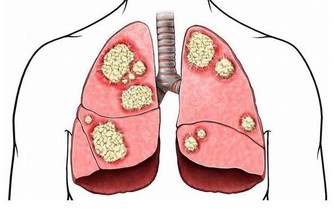

一說起尿毒症可能大家現在都不太陌生,尿毒症是指身體不能通過腎臟產生尿液,把身體代謝所產生的廢物,還有多餘的水分排出體外而引起的毒害,尿毒症是腎功能下降

腎臟是 所以在我們的日常生活當中,需要通過合理的方式來保護腎臟的健康,以免腎臟功能受到損傷,影響身體健康。

結語:尿毒症對身體的傷害是毀滅性的,目前的醫療水平無法徹底根治尿毒症。那麼我們就應該防患於未然,改變不良的生活習慣,這樣才能更好的保護自己的腎臟。